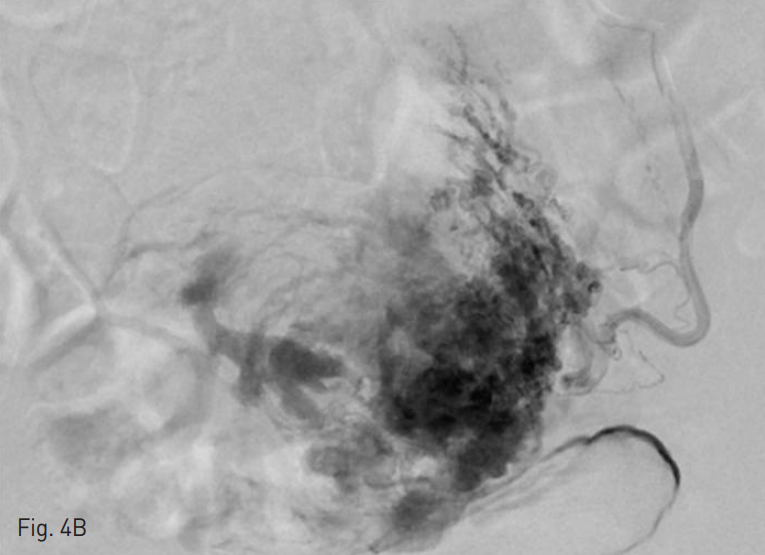

artery)으로부터도 혈류가 공급되는 소견 보여 (Fig. 4) 이들 혈관을 초선택하여 좌측 폐쇄동맥은 젤폼과 미세코일 (4mm x 4cm 2EA, Tornado, Cook, Bloomington, IN, USA)로, 좌측 방광동맥은 젤폼으로 색전술을 시행하였다. 시술 익일에 시행한 질식 초음파 및 복부전산화 단충촬영 소견 상에서 여전히 과혈관성 종괴가 관찰되어 5일 후 추가 색전술이 다시 의뢰되었다. 양측 외장골동맥 (ex ternal iliac artery)의 하복벽동맥 (inferior epigastric artery)으로부터 기시하는 원인대동맥 (round ligament artery)으로부터 자궁의 동정맥 기형이 여전히 혈류를 공급받고 있었다(Fig. 5). 5Fr Cobra 카테터 및 2.2Fr 미세도관을 이용하여 양측 원인대동맥을 초선택한 후 Polyvinyl alcohol particles (355-500um 1ival, Contour; Boston Scientific, Cork Ireland)와 젤폼을 이용하여 색전술을 시행하였다. 색전술 후 시행한 골반동맥 조영술상에서 자궁 동정맥 기형 소견이 없음을 확인하고 시술을 종료하였다.

Fig. 4

Selective angiography demonstrates the uterine arteriovenous malformation fed by both uterine arteries (A~B) and multiple fine branches from left vesical artery (C) and left obturator artery (D).